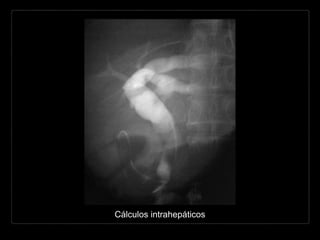

CÁLCULOS INTRAHEPÁTICOS

• raros

• común en pacientes con

colangitis piógena

recurrente

• común en conductos de

calibre mayor

• lóbulo hepático izquierdo

(5x)

Hallazgos por TC y RM

• similares a los de la colédocolitiasis